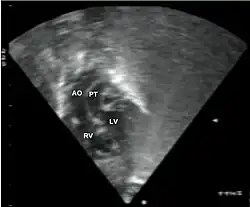

Subcostal echocardiographic view showing discordant ventriculoarterial connections together with the presence of parallel, rather than crossing, great arteries arising from the ventricles.

Echocardiogram in transposition of the great arteries. This subcostal view shows the left ventricle giving rise to a vessel that bifurcates, which is thus identified as the pulmonary artery.